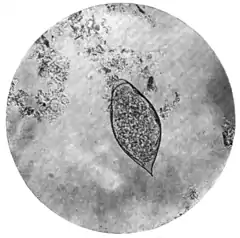

The ovum.—On microscopical examination the uterus of the female bilharzia is found to be stuffed with ova of a peculiar and characteristic shape. They are oval, each egg on an average measuring about 0·16 mm. in length by 0·06 mm. in breadth, and one end of the ovum is provided with a short, stout, and very definite spine. (Plate XIII., Fig. 1.)

The free larva (Fig. 132).—In newly voided urine the ovum

presents a somewhat brownish appearance, and generally contains a ciliated larva (miracidium). After a time the larva may escape through a longitudinal rupture in the shell. It then swims about, but, unless supplied with fresh water, soon perishes. If the urine be freely diluted with water, the larva not only escapes more quickly from the shell but also continues to live, swimming and gyrating very actively, for a considerable time. While swimming, the body of the little animal undergoes many changes of shape. For the most part, when advancing, it is oblong, tapering somewhat posteriorly; when more stationary it tends to assume a spherical form. It moves by means of the cilia which, with the exception of the minute papillary beak, thickly cover the entire body. On carefully examining the larva, a canal may be traced from the beak into what looks like a rudimentary stomach; on both sides of this, two much smaller gland-like organs can be seen, from each of which a delicate tube passes forwards and opens, apparently, somewhere in the neighbourhood of the beak.

| Fig. 1.—Terminal-spined egg of Schistosomum hæmatobium. (Microphotograph: Dr. Bell.) |